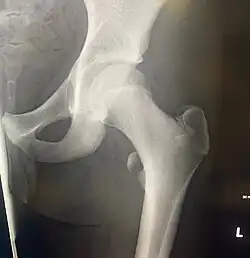

Lesser trochanter avulsion fracture

The lesser trochanter can be involved in an avulsion fracture.[4]